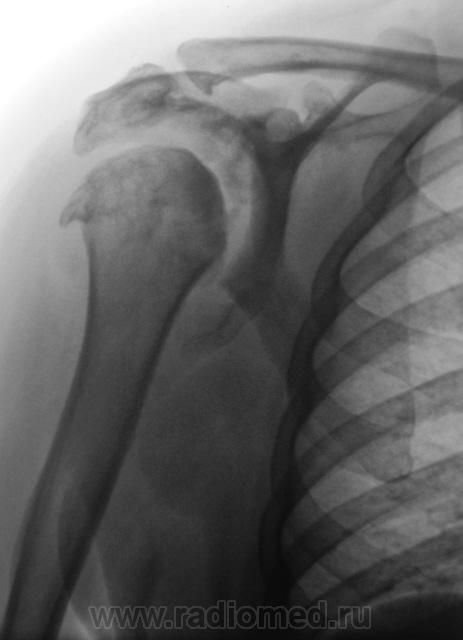

Где же подевался плечевой отросток лопатки? Что за мягкотканный компонент в подмышечной области? Костные разрастания само собой...это видно...

Если бы и конгруэнтность суставной поверхности плечевой кости была бы нарушена - предположил бы сирингомиелию...пока в раздумии, задачка не из простых....

Да патология весьма интересная. Мы долго ломали голову взвешивая все "ЗА", проводя диф. диагностику между сирингомиелией и волчанкой.